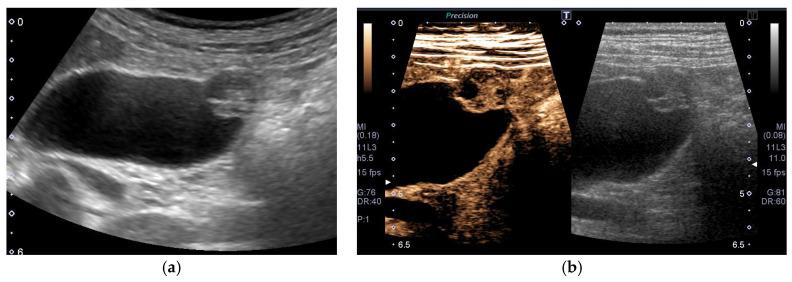

The most important role of ultrasound (US) in the management of gallbladder (GB) lesions is to detect lesions earlier and differentiate them from GB carcinoma (GBC). To avoid overlooking lesions, postural changes and high-frequency transducers with magnified images should be employed. GB lesions are divided into polypoid lesions (GPLs) and wall thickening (GWT). For GPLs, classification into pedunculated and sessile types should be done first. This classification is useful not only for the differential diagnosis but also for the depth diagnosis, as pedunculated carcinomas are confined to the mucosa. Both rapid GB wall blood flow (GWBF) and the irregularity of color signal patterns on Doppler imaging, and heterogeneous enhancement in the venous phase on contrast-enhanced ultrasound (CEUS) suggest GBC. Since GWT occurs in various conditions, subdividing into diffuse and focal forms is important. Unlike diffuse GWT, focal GWT is specific for GB and has a higher incidence of GBC. The discontinuity and irregularity of the innermost hyperechoic layer and irregular or disrupted GB wall layer structure suggest GBC. Rapid GWBF is also useful for the diagnosis of wall-thickened type GBC and pancreaticobiliary maljunction. Detailed B-mode evaluation using high-frequency transducers, combined with Doppler imaging and CEUS, enables a more accurate diagnosis.

超声(US)在胆囊(GB)病变管理中的最重要作用是更早地检测病变并将其与胆囊癌(GBC)区分开来。为避免漏诊病变,应采用体位改变以及具有放大图像的高频探头。GB病变分为息肉样病变(GPLs)和胆囊壁增厚(GWT)。对于GPLs,应首先分为有蒂型和无蒂型。这种分类不仅有助于鉴别诊断,也有助于深度诊断,因为有蒂癌局限于黏膜层。胆囊壁血流(GWBF)快速、多普勒成像时彩色信号模式不规则以及对比增强超声(CEUS)静脉期不均匀强化均提示GBC。由于GWT可在多种情况下出现,将其细分为弥漫性和局灶性形式很重要。与弥漫性GWT不同,局灶性GWT是GB特有的,且GBC发生率更高。最内层高回声层的连续性中断和不规则以及GB壁层结构不规则或破坏提示GBC。快速GWBF对壁增厚型GBC和胰胆管汇合异常的诊断也有帮助。使用高频探头进行详细的B超评估,结合多普勒成像和CEUS,可实现更准确的诊断。